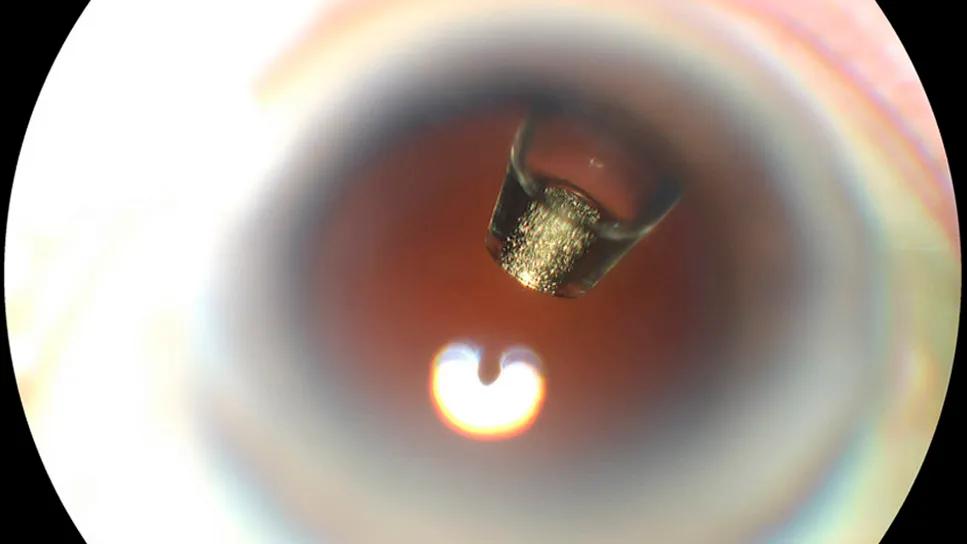

Ranibizumab port delivery system inside an eye

The ranibizumab port delivery system (shown inside the eye of a patient, above) was originally approved after the phase 3 Archway study. Archway was an open-label, randomized clinical trial involving patients previously treated for nAMD. The primary endpoint was the change in best-corrected visual acuity (BCVA), which the treatment did achieve. And, the center point thickness of the retina didn’t change a bit when compared with monthly ranibizumab injection.